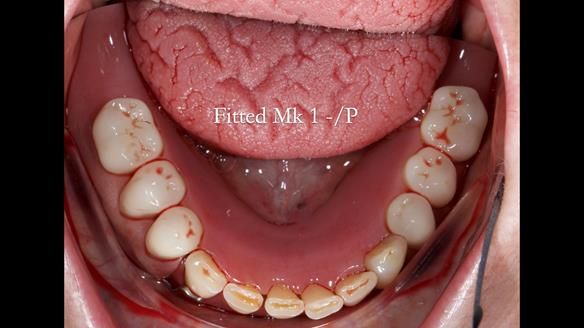

This newsletter describes the full protocol workflow of a complete upper denture and a lower partial denture for Jo.

The clinical situation and treatment process is shown in detail below. I provided the clinical work. Rowan Garstang provided the technical work. This treatment took 25 visits over a period of 12 months.